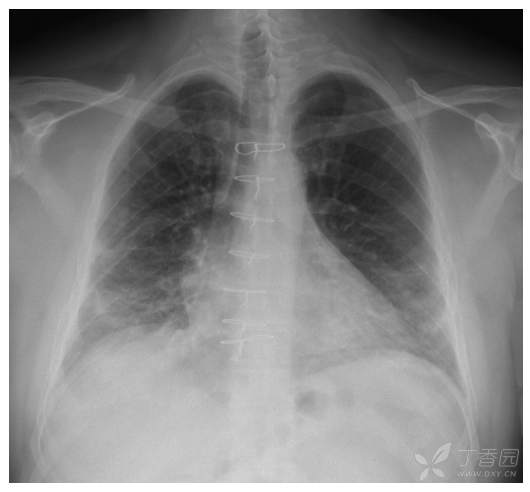

57岁男子干咳气短1月,病理已经做,诊断?

男性 57 岁因干咳和气短一月就诊 。

患者2 个月前经历了一次干咳和气短。临床诊断他患有上呼吸道疾病 感染,仅保守治疗7天后症状消失。一个月后,干咳和气短又发,接受了为期5天的治疗口服阿奇霉素疗程后症状没有任何改善。

因怀疑间质性肺疾病,予电视胸腔镜下肺活检,病理如下: